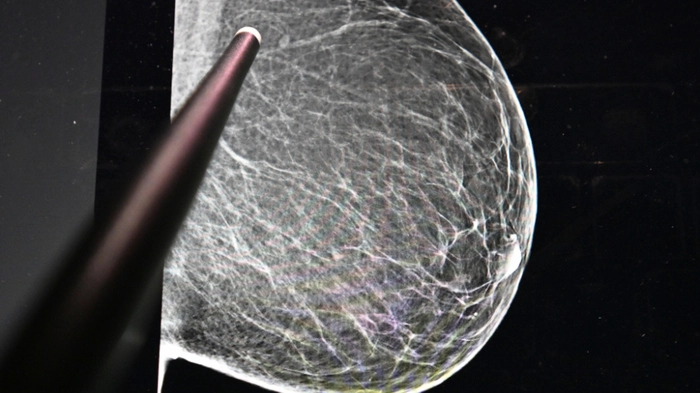

Weltweit starke Zunahme von Brustkrebs prognostiziert

Brustkrebs ist nach wie vor die häufigste Krebsart bei Frauen weltweit. Die Zahl der jährlichen Fälle wird von 2,3 Millionen im Jahr 2023 bis 2050 voraussichtlich auf über 3,5 Millionen steigen. Die reichen Länder der Welt sehen eine Stabilisierung auf hohem Niveau. Das hat eine neue Studie für 204 Staaten der Erde ergeben, die jetzt in "Lancet Oncology" erschienen ist.

3,5 Millionen Fälle für 2050 erwartet | 3,5 Millionen Fälle für 2050 erwartet

3,5 Millionen Fälle für 2050 erwartet